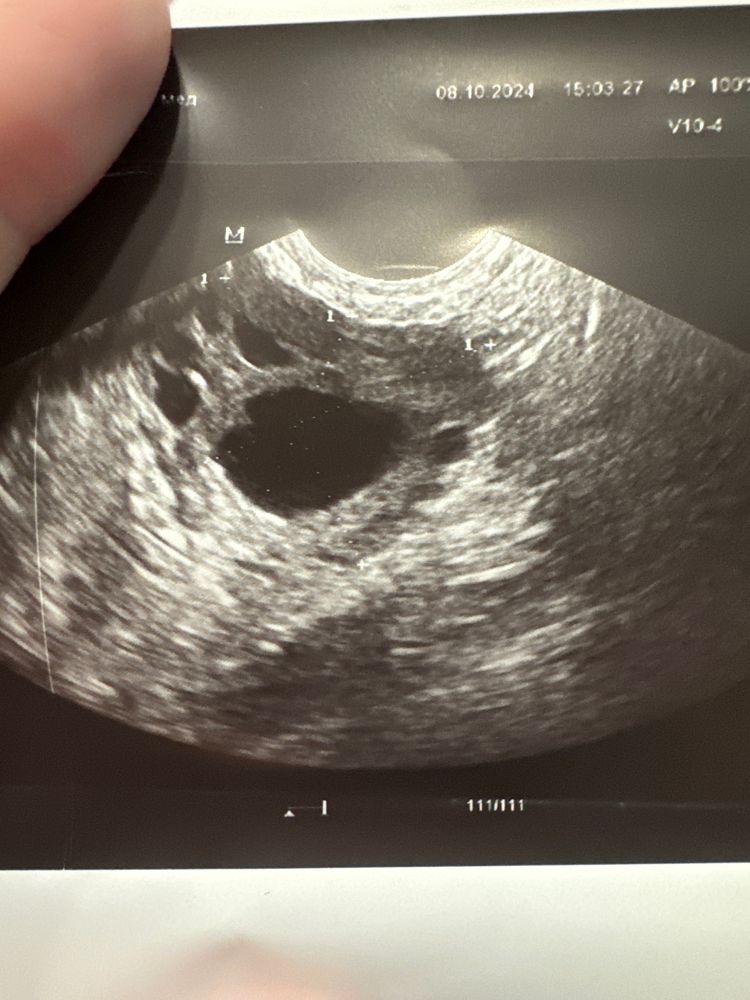

Дарья, да он как-то медленно растет.. и формы такой странной.. вытянутый более, что ли.. вот он был на 1 фотке и вот 2 это сейчас 🤔 Изображение Изображение

Фолликул вырос всего на 2 мм